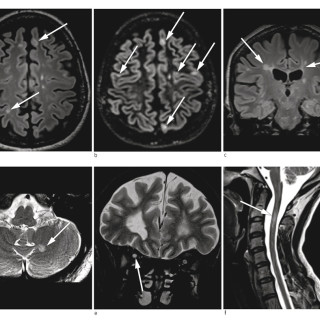

En kvinne fikk forverring av en hodepine som hadde debutert flere måneder i forveien. Hun utviklet deretter uvanlige kognitive symptomer og ble innlagt i sykehus. Pasienten, som var i 40-årene, hadde fra tidligere astma og var slankeoperert med gastrisk bypass. Det siste halvåret før innleggelsen hadde hun vært sykmeldt grunnet en oksipital, bilateral hodepine som oppsto under en arbeidskonflikt, men vedvarte trass i omplassering i ny stilling. Hodepinen hadde et fluktuerende forløp, med hodepinefrie dager. Den siste måneden var imidlertid hodepinen blitt konstant, og kvinnen hadde tatt...